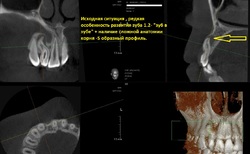

В стоматологию МС обратилась молодая девушка с жалобами на боль в области зуба на верхней челюсти справа.Ранее пациентка обращалась уже в несколько клиник , но после оценки докторами рентгеновского исследования данного зуба предлагался только один неутешительный вердикт- удаление.После оценки 3D рентген исследования зуба стало понятно , что так смущало других докторов.В данном случае в зубе оказалась достаточно редкая особенность развития- Dens invaginatus (зуб в зубе), простыми словами внутри зуба находился еще один маленький недоразвитый зуб, также особую сложность придавал так называемый S образный изгиб корня.